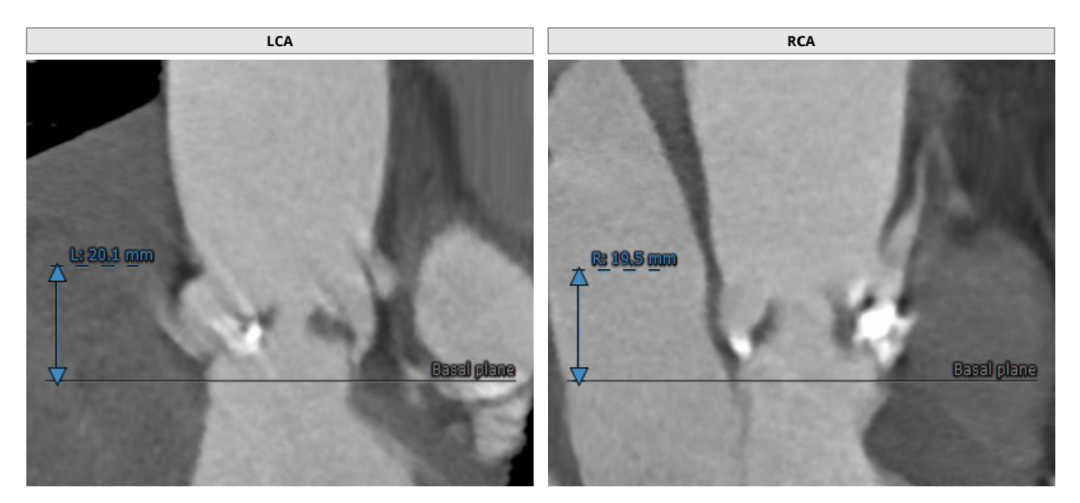

CT评估

瓣环直径:24.5mm,左室流出道直径:25.4mm

主动脉窦:25.9*36.9mm,STJ:30.4mm

升主动脉直径:36.5,心脏夹角:59度

左冠高度:20.1mm,右冠高度:19.5mm